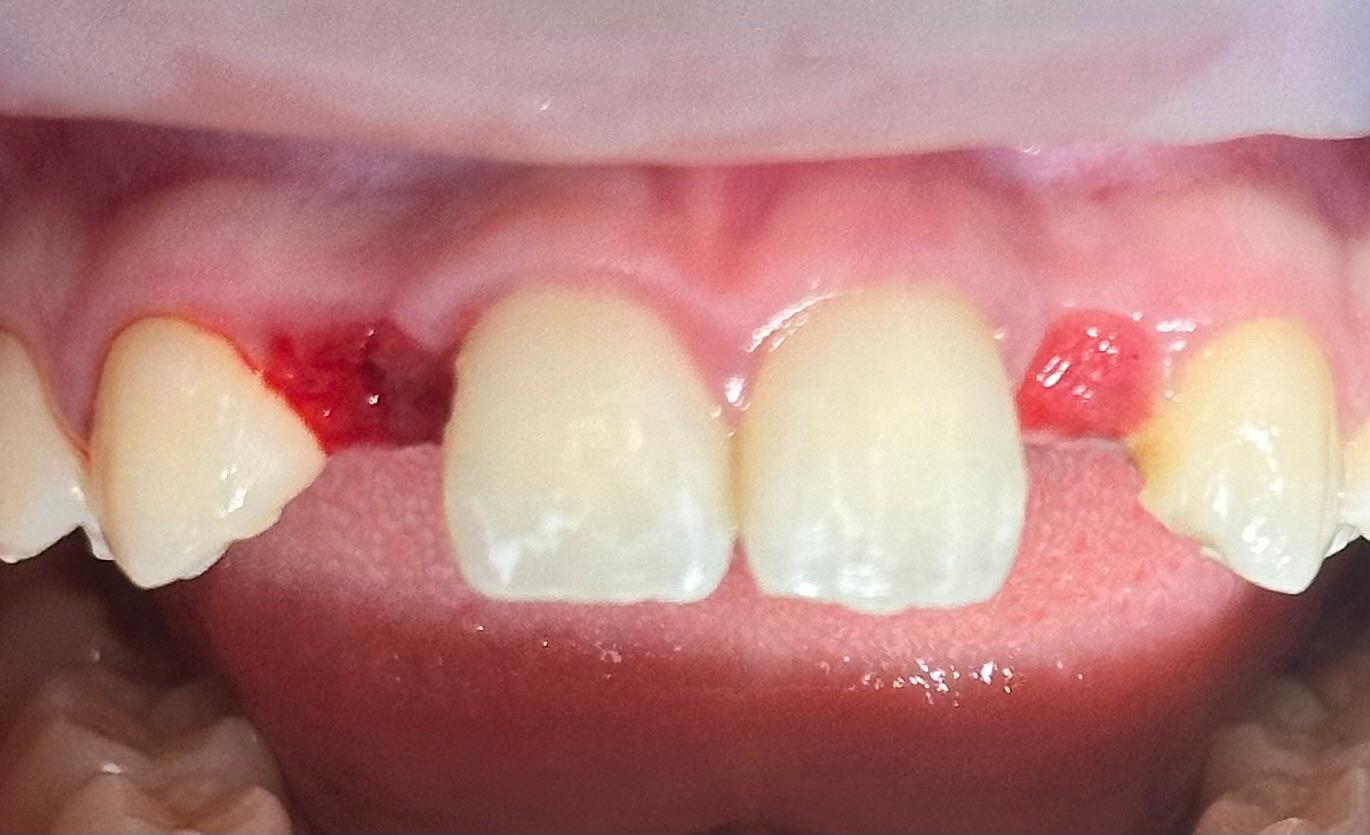

Muchos de nuestros pacientes sufren de agenesia, una condición en la que los dientes definitivos (comúnmente los laterales) nunca llegan a salir. Esto suele dejar un espacio estrecho y un hueso que, al no haber tenido nunca la raíz de un diente, es muy delgado.

En lugar de abrir grandes heridas para colocar hueso artificial, utilizamos implantes de última generación conocidos como monobloque. Estos implantes están diseñados específicamente para ser colocados en espacios muy reducidos, aprovechando hasta el último milímetro de tu hueso natural.

Lo que realmente nos diferencia es la carga inmediata. No queremos que salgas de nuestra clínica con un hueco en tu sonrisa. En el mismo momento de la cirugía, preparamos coronas provisionales que no solo devuelven la estética, sino que ayudan a que tu encía se cure con la forma perfecta.